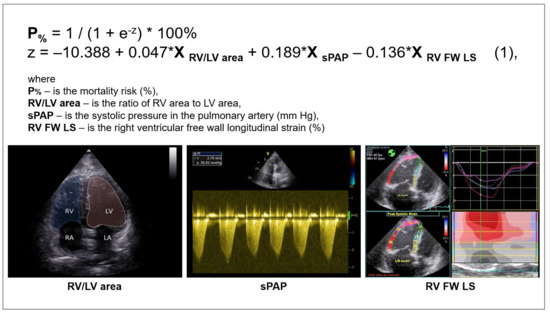

3.2. Logistic Regression Analysis and Prognostic Model Quality Assessment